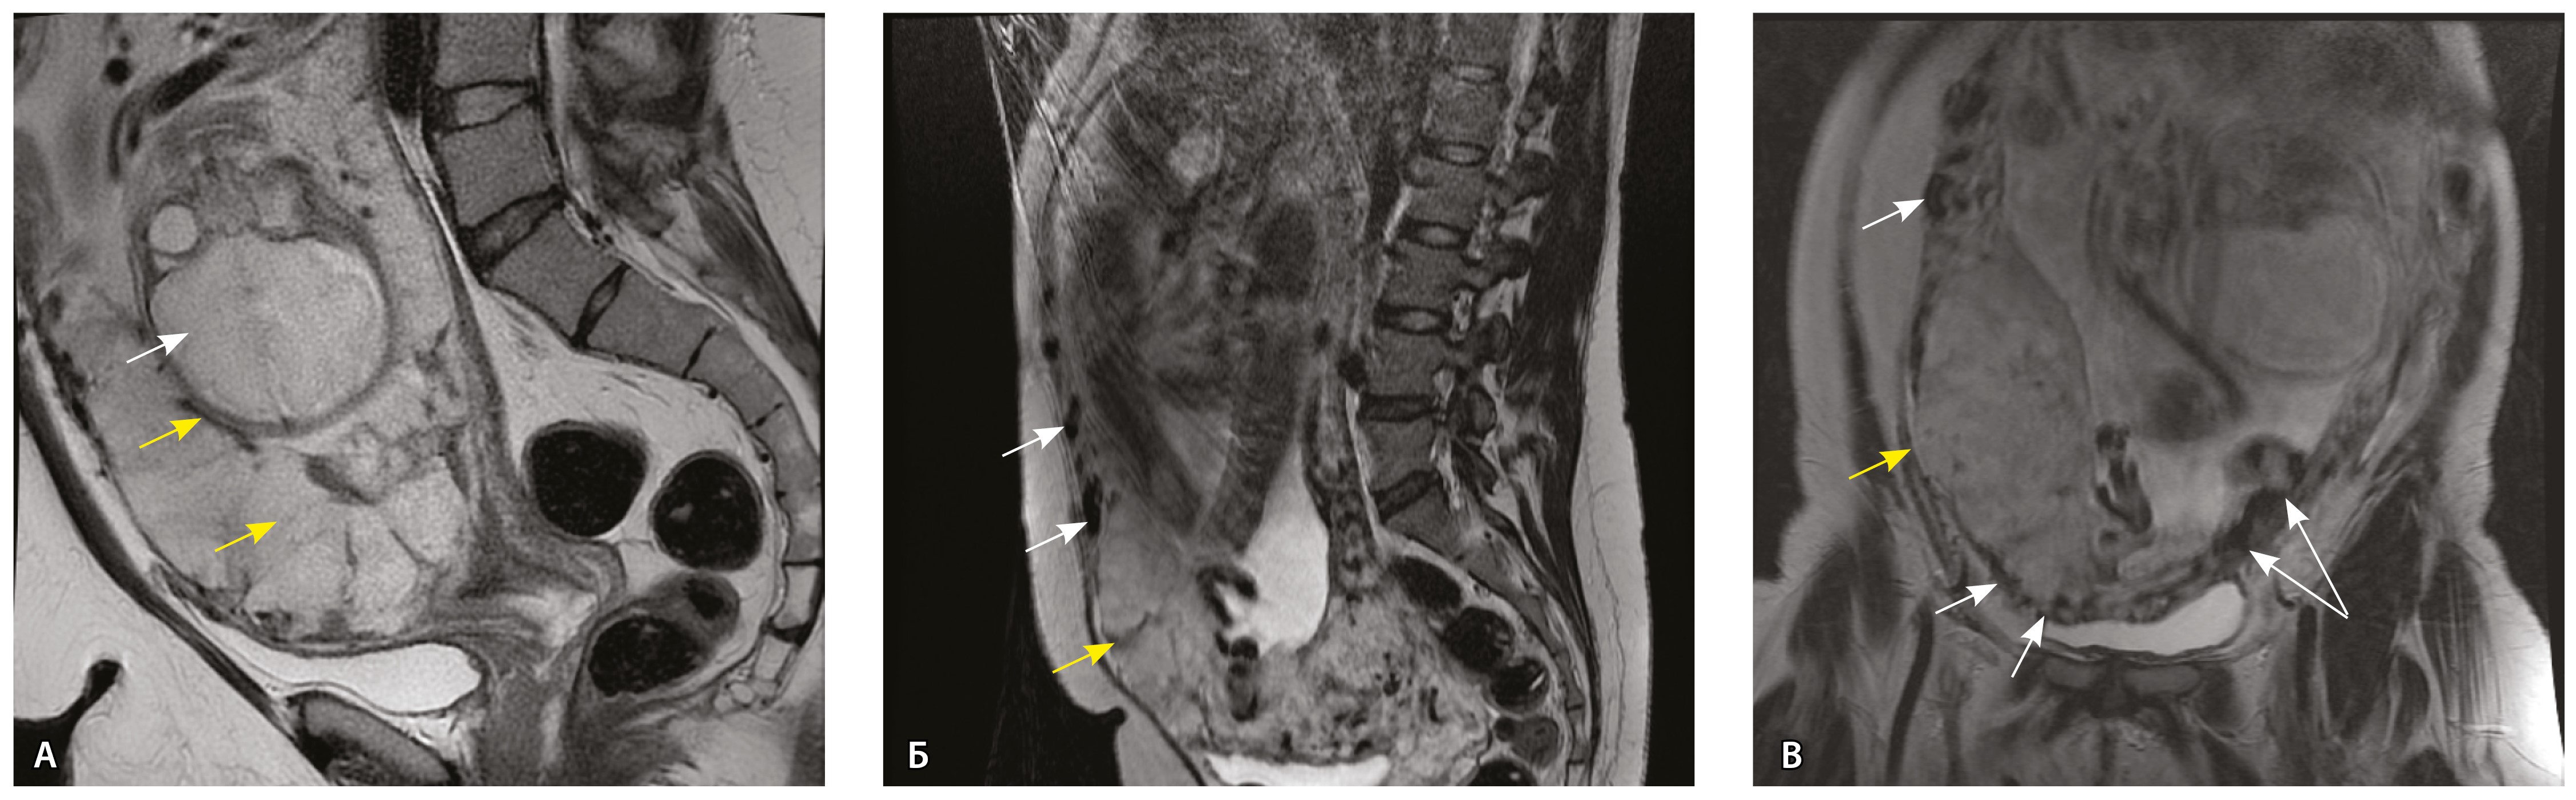

Сосуды 3-го типа. Внутриматочная гиперваскуляризация с дефицитом толщины миометрия, преимущественно сосуды срединного слоя, аналог pl. increta PAS 2, гестационная перестройка радиальных артерий (рис. 7).

Рис. 7. Беременность 34 недели, pl. increta, PAS 2 по FIGO. На магнитно-резонансных томограммах в режиме Т2-взвешенного изображения в сагиттальной (A, Б) и фронтальной (В) плоскостях определяется внутриматочная гиперваскуляризация с наличием многочисленных сливающихся сосудов в толще стенки матки, в области плацентарной площадки (белые стрелки); в нижнем маточном сегменте – выраженное истончение стенки матки, рубца от кесарева сечения с формированием маточной грыжи (желтые стрелки)

Рис. 10. Беременность 33 недели, pl. percreta, PAS 3a по FIGO. На магнитно-резонансных томограммах в режиме Т2-взвешенного изображения в сагиттальной (A) и фронтальной (Б, В) плоскостях определяется внутриматочная гиперваскуляризация (желтые стрелки) и гиперваскуляризация в области выраженно истонченного нижнего маточного сегмента, с наличием многочисленных анастомозирующих сосудов по поверхности матки (белые стрелки); стенка матки в данной области представлена ретроплацентарными сосудами